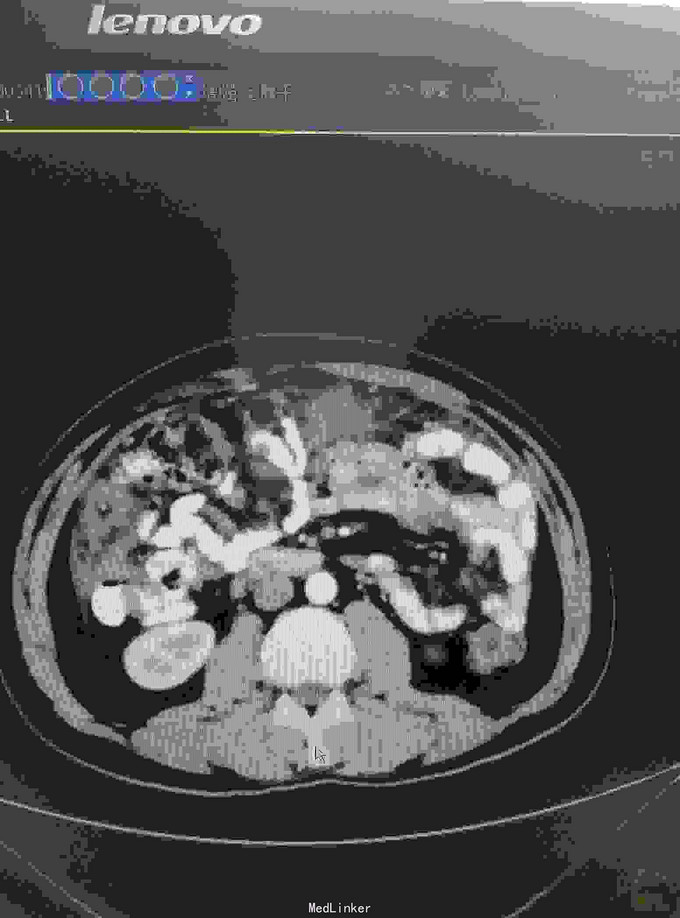

患者15年6月因腹胀就诊某医院行CT:疑似自发性腹膜炎,给予抗炎治疗。9月15日送检腹水发现增生间皮细胞。后去省影像中心行CT示:腹膜广泛增厚,强化,符合转移。后就诊我院腹膜肿物穿刺病理:促结缔组织增生性小园细胞瘤。后期贝伐单抗,IFO,THP,VCR,治疗。目前治疗中……